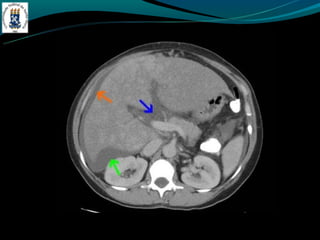

TROMBOSE DA VEIA PORTA

-Incidência de 5% na hipertensão portal e próximo de 30% no

CHC

-TC: Esplenomegalia, formação de colaterais, ascite, e pode ter

alta atenuação na fase arterial.

TROMBOSE DA VEIAPORTA -Complicação de cirrose -Invasão ou compressão tumoral -Hipercoagulabilidade -Inflamação -Incidência de 5% na hipertensão portal e próximo de 30% no CHC -TC: Esplenomegalia, formação de colaterais, ascite, e pode ter alta atenuação na fase arterial. -RM: trombo agudo hiper em T1 e T2, crônico hipo em T1 e hiper em T2.